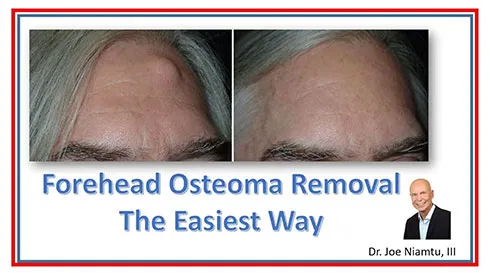

The images below show selected before and after cases of endoscopic osteoma removal.